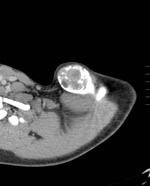

На МРТ врач обнаружил огромную кисту в области ключицы. Киста разрослась настолько, что косточка в ключице была вынуждена выгибаться как может.

Тянуть не буду с результами. Вообщем есть подозрение что это опухоль.

Злокачественная она или нет, пока не могут сказать. В любом случае её будут полностью удалять, вместе с частью сломанной косточки.